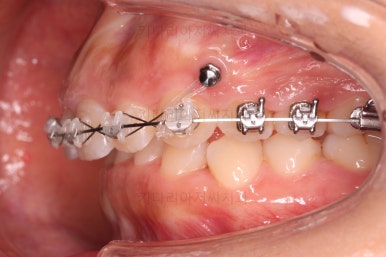

우선 윗니부터 가지런하게 해줍니다.

앞니쪽에는 미니스크류를 식립했는데요.

과개교합 개선, 교합 개선, 거미스마일(잇몸웃음) 개선 등 여러 가지 목적을 동시에 달성할 수 있어요.

윗니가 어느 정도 가지런해지면 아랫니도 장치가 들어갑니다.

이번 부산옥니교정 환자분이 선택하신 장치는 엠파워인데 윗니는 덜 보이는 세라믹, 아랫니는 메탈입니다.

같은 엠파워 장치이기 때문에 이렇게 섞어 써도 문제가 전혀 없는데요.

흔히 아시는 클리피씨로 하자면 윗니는 클리피씨 + 아랫니는 클리피엠(M)인 셈이죠.

윗니는 세람기으로 해서 심미성을 강조하고 아랫니는 좀 더 부피가 작고 강하여 과개교합 교정에 유리하며 저렴하기도 한 메탈로 했습니다.

장치 부착 직후의 모습입니다.

웃을 때도 주로 윗니만 보이기 때문에 아랫니는 메탈로 해도 큰 문제 없어보이네요.